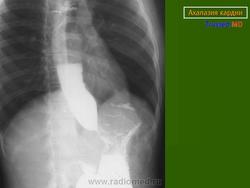

Ахалазия

Случаи и цифры

Дело 1

Случай 2

Случай 3